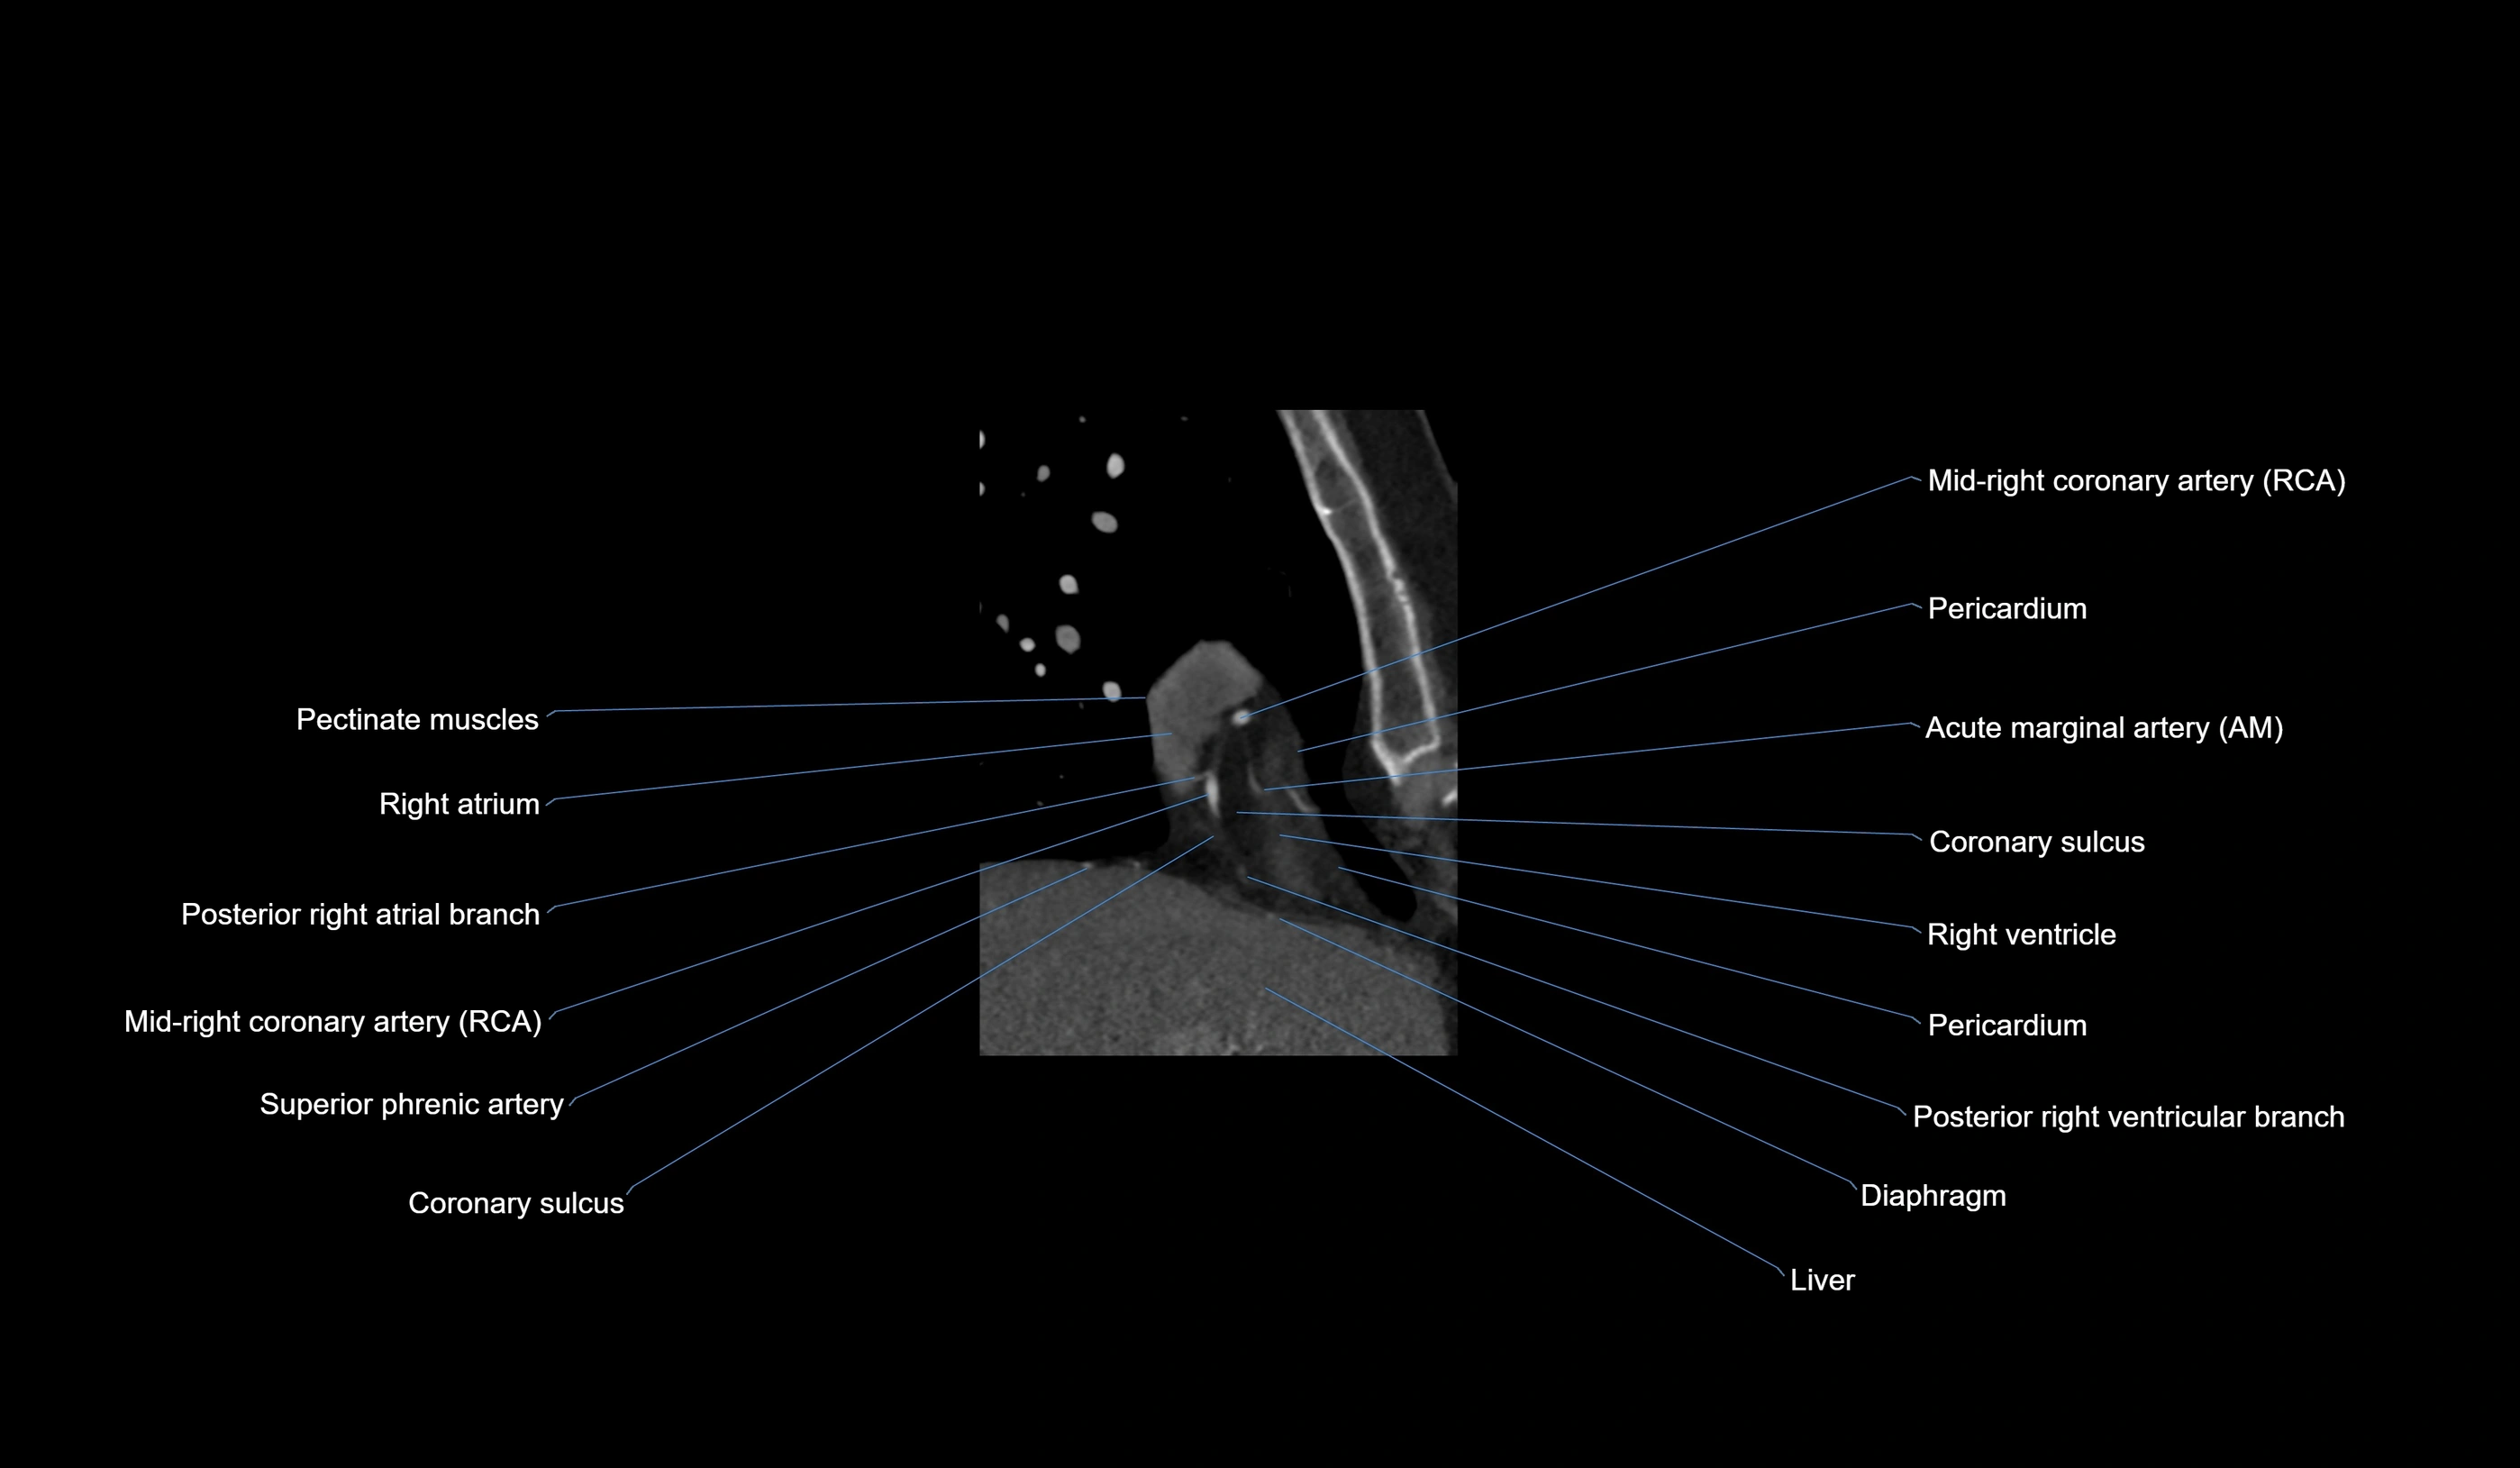

- Acute marginal artery (AM)

The acute marginal artery (AM) is one of the main branches of the right coronary artery (RCA). It typically arises from the mid to distal segment of the RCA and courses along the acute margin (right inferolateral border) of the right ventricle. The AM artery runs within the epicardial fat and supplies blood primarily to the right ventricular free wall.

The number and size of AM branches vary: most individuals have one dominant acute marginal artery, but some may have multiple smaller branches. The vessel is of high clinical importance in right ventricular infarction, since occlusion or disease of the RCA or AM branch can compromise right ventricular contractility and systemic venous return.

CT Coronary Angiography (CCTA):

-

Best non-invasive modality for acute marginal artery visualization

Shows origin, course along the acute margin, and right ventricular branches

Detects stenosis, occlusion, calcified and non-calcified plaques, aneurysm, or anomalous course

Multiplanar reformats and 3D reconstructions help in pre-PCI and surgical planning

Critical for assessing right ventricular infarction risk in RCA disease

CT images